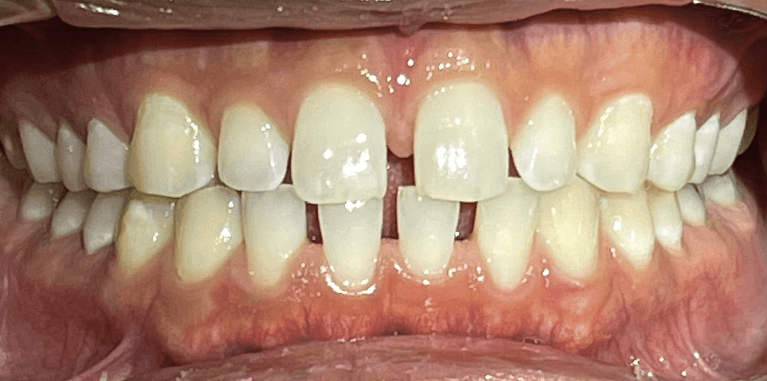

Invisalign Orthodontic treatment completed in 8 months to straighten teeth and improve esthetics.